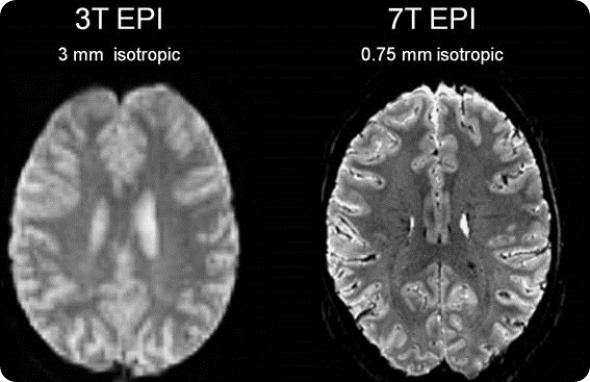

Stronger magnet fields increase the signal-to-noise ratio of the MRI signal. This increase in signal to noise can then be used to increase the spatial or temporal resolution of the image. Simply put, the higher the magnetic field strength, the more detail we can see inside the body.

Most MRI scanners operate between 1.5 Tesla and 3 Tesla. Due to benefits of the increased resolution at higher filed strengths SMT have developed a ground breaking 7 Tesla system, the MAGNETOM Terra. This new system has been designed to meet the demands of both researchers and clinicians.